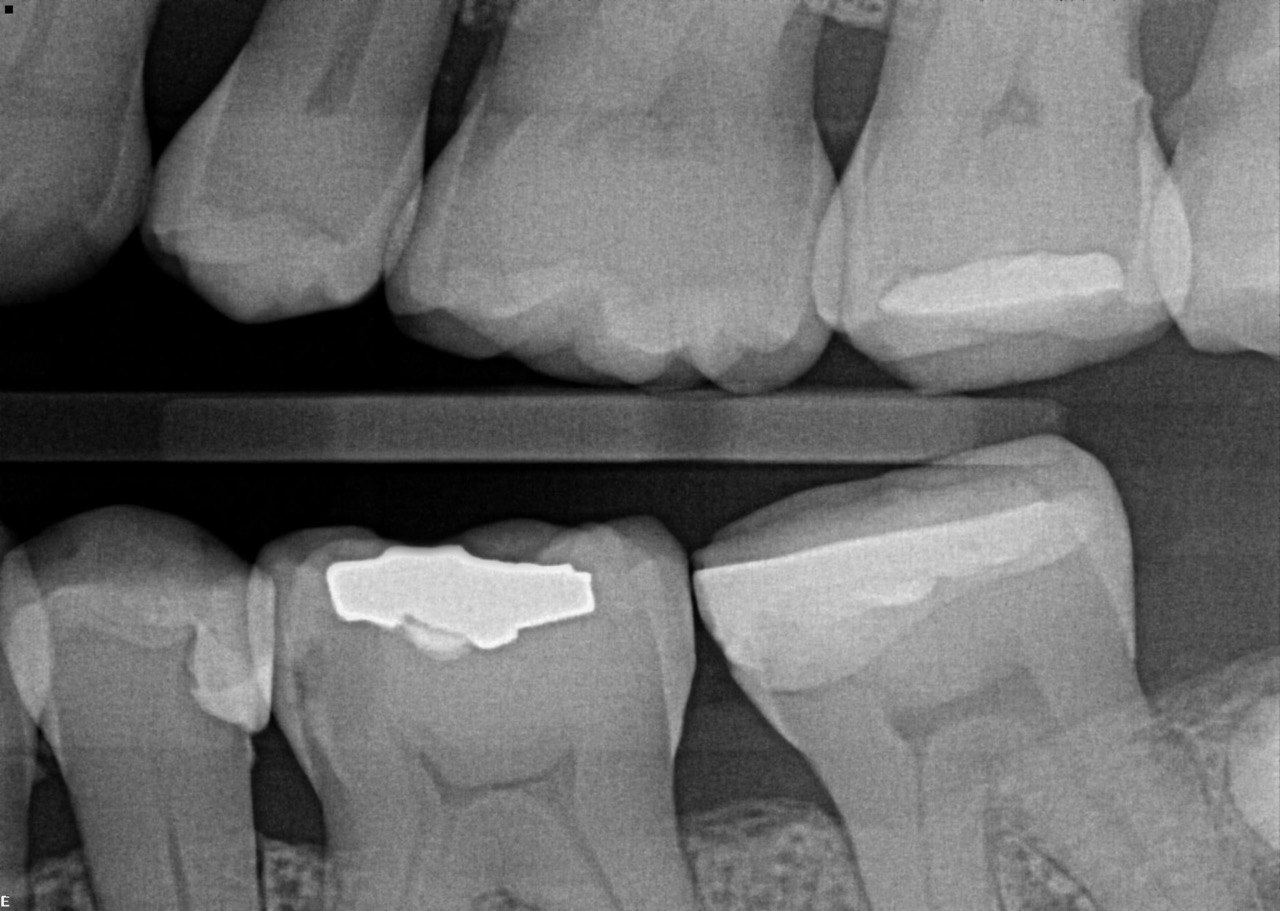

1. What surface require restoration?